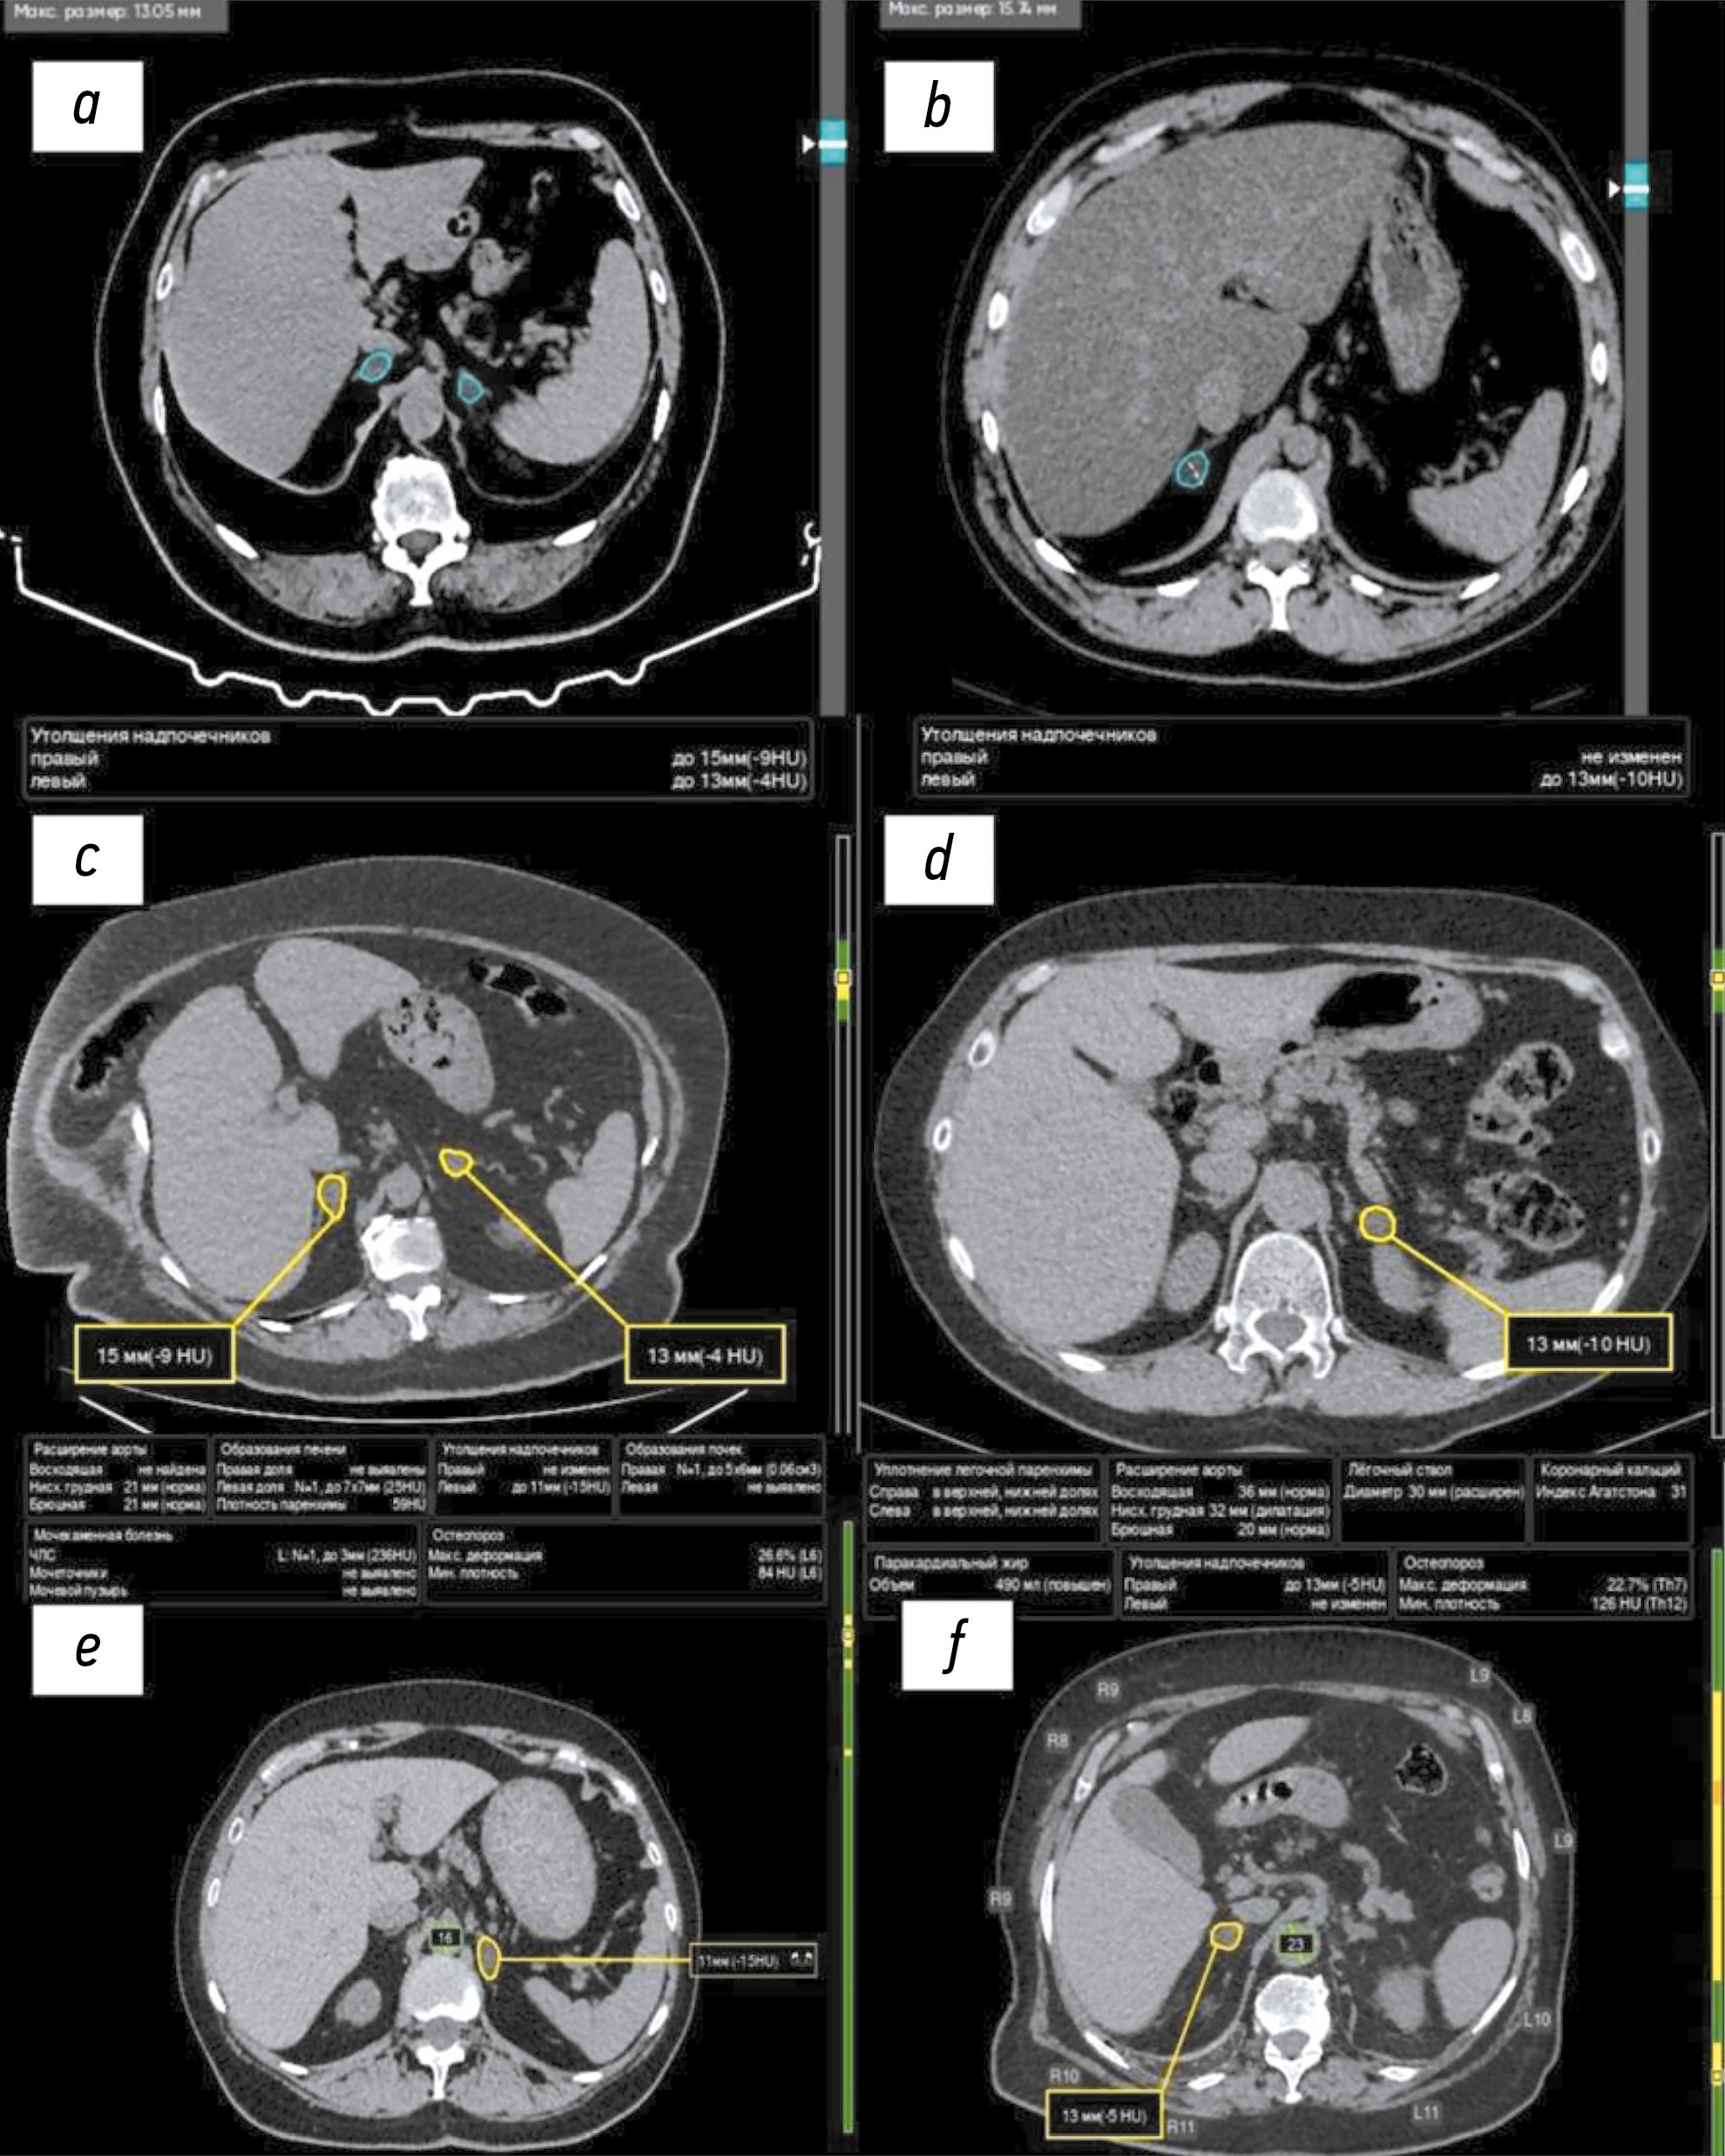

Примеры работы ИИ-сервисов для диагностики новообразований надпочечников продемонстрированы на рис. 1.

Рис. 1. Примеры работы сервисов искусственного интеллекта для выявления новообразований надпочечников по данным компьютерной томографии органов грудной клетки и брюшной полости: a, b — моносервис на основе искусственного интеллекта-1 для диагностики новообразований надпочечников: голубым контуром обведены новообразования надпочечников на изображениях компьютерной томографии органов брюшной полости; c, d — моносервис на основе искусственного интеллекта-2 для диагностики новообразований надпочечников: жёлтым контуром обведены новообразования надпочечников на изображениях компьютерной томографии органов брюшной полости; e, f — комплексный сервис на основе искусственного интеллекта-2 для диагностики новообразований надпочечников: жёлтым контуром обведено образование левого надпочечника (e) на изображении компьютерной томографии органов брюшной полости и правого надпочечника (f) на изображении компьютерной томографии органов грудной клетки.